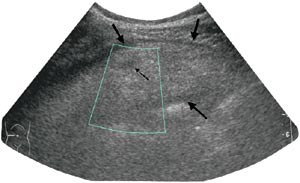

Pasient 2. En 42 år gammel mann, tidligere appendektomert og operert for etterfølgende adheranseileus, kom inn med konstante smerter i høyre nedre kvadrant av halvannet døgns varighet. Han hadde redusert matlyst, men ikke oppkast. Ved klinisk undersøkelse var han subfebril og hadde en palpabel oppfylling til høyre for umbilicus og tegn til peritonitt. Ultrasonografi viste, svarende til palpasjonsfunnet, en ekkorik, relativt homogen oppfylling med et par små sentrale hypoekkoiske foci. Den var velavgrenset fra tarm, 3 x 8 cm stor og med litt ødem omkring (fig 3). CT fremstilte i samme lokalisasjon en skarpt avgrenset lavattenuerende, inhomogen oval oppfylling med omliggende ødem. Den var 10 x 4 cm stor og hadde utseende som ødematøst fettvev (fig 4). Røntgen thorax og oversikt abdomen var upåfallende. Preoperativ diagnose var uspesifisert oppfylling eller infiltrat, sannsynligvis uten relasjon til tarm. Pasienten ble laparotomert, og det ble funnet torsjon av en del av omentet, med begynnende nekrose. Affisert fettvev ble fjernet og diagnosen verifisert ved histologisk undersøkelse.

Ultrasonografisk viser lesjonen seg som en rund eller oval ekkorik oppfylling lokalisert til ømhetens punctum maximum (1, 6) – (8). Oppfyllingen er ikke-komprimerbar og ofte adherent til peritoneum, sistnevnte demonstreres best i sagittalplan, hvor man under respirasjon kan observere lesjonens manglende bevegelighet i forhold til øvrig intraperitonealt innhold (7). Det ses ofte et 1 – 2 mm tynt, hypoekkoisk sjikt rundt oppfyllingen. Andre beskrevne assosierte funn er hypoekkoiske foci inni lesjonen som sannsynligvis representerer hemoragiske forandringer, fortykkelse av tilgrensende tarmvegg og peritoneum og masseeffekt med dislokasjon av tarm. Ved bruk av fargedoppler ses manglende blodstrøm.